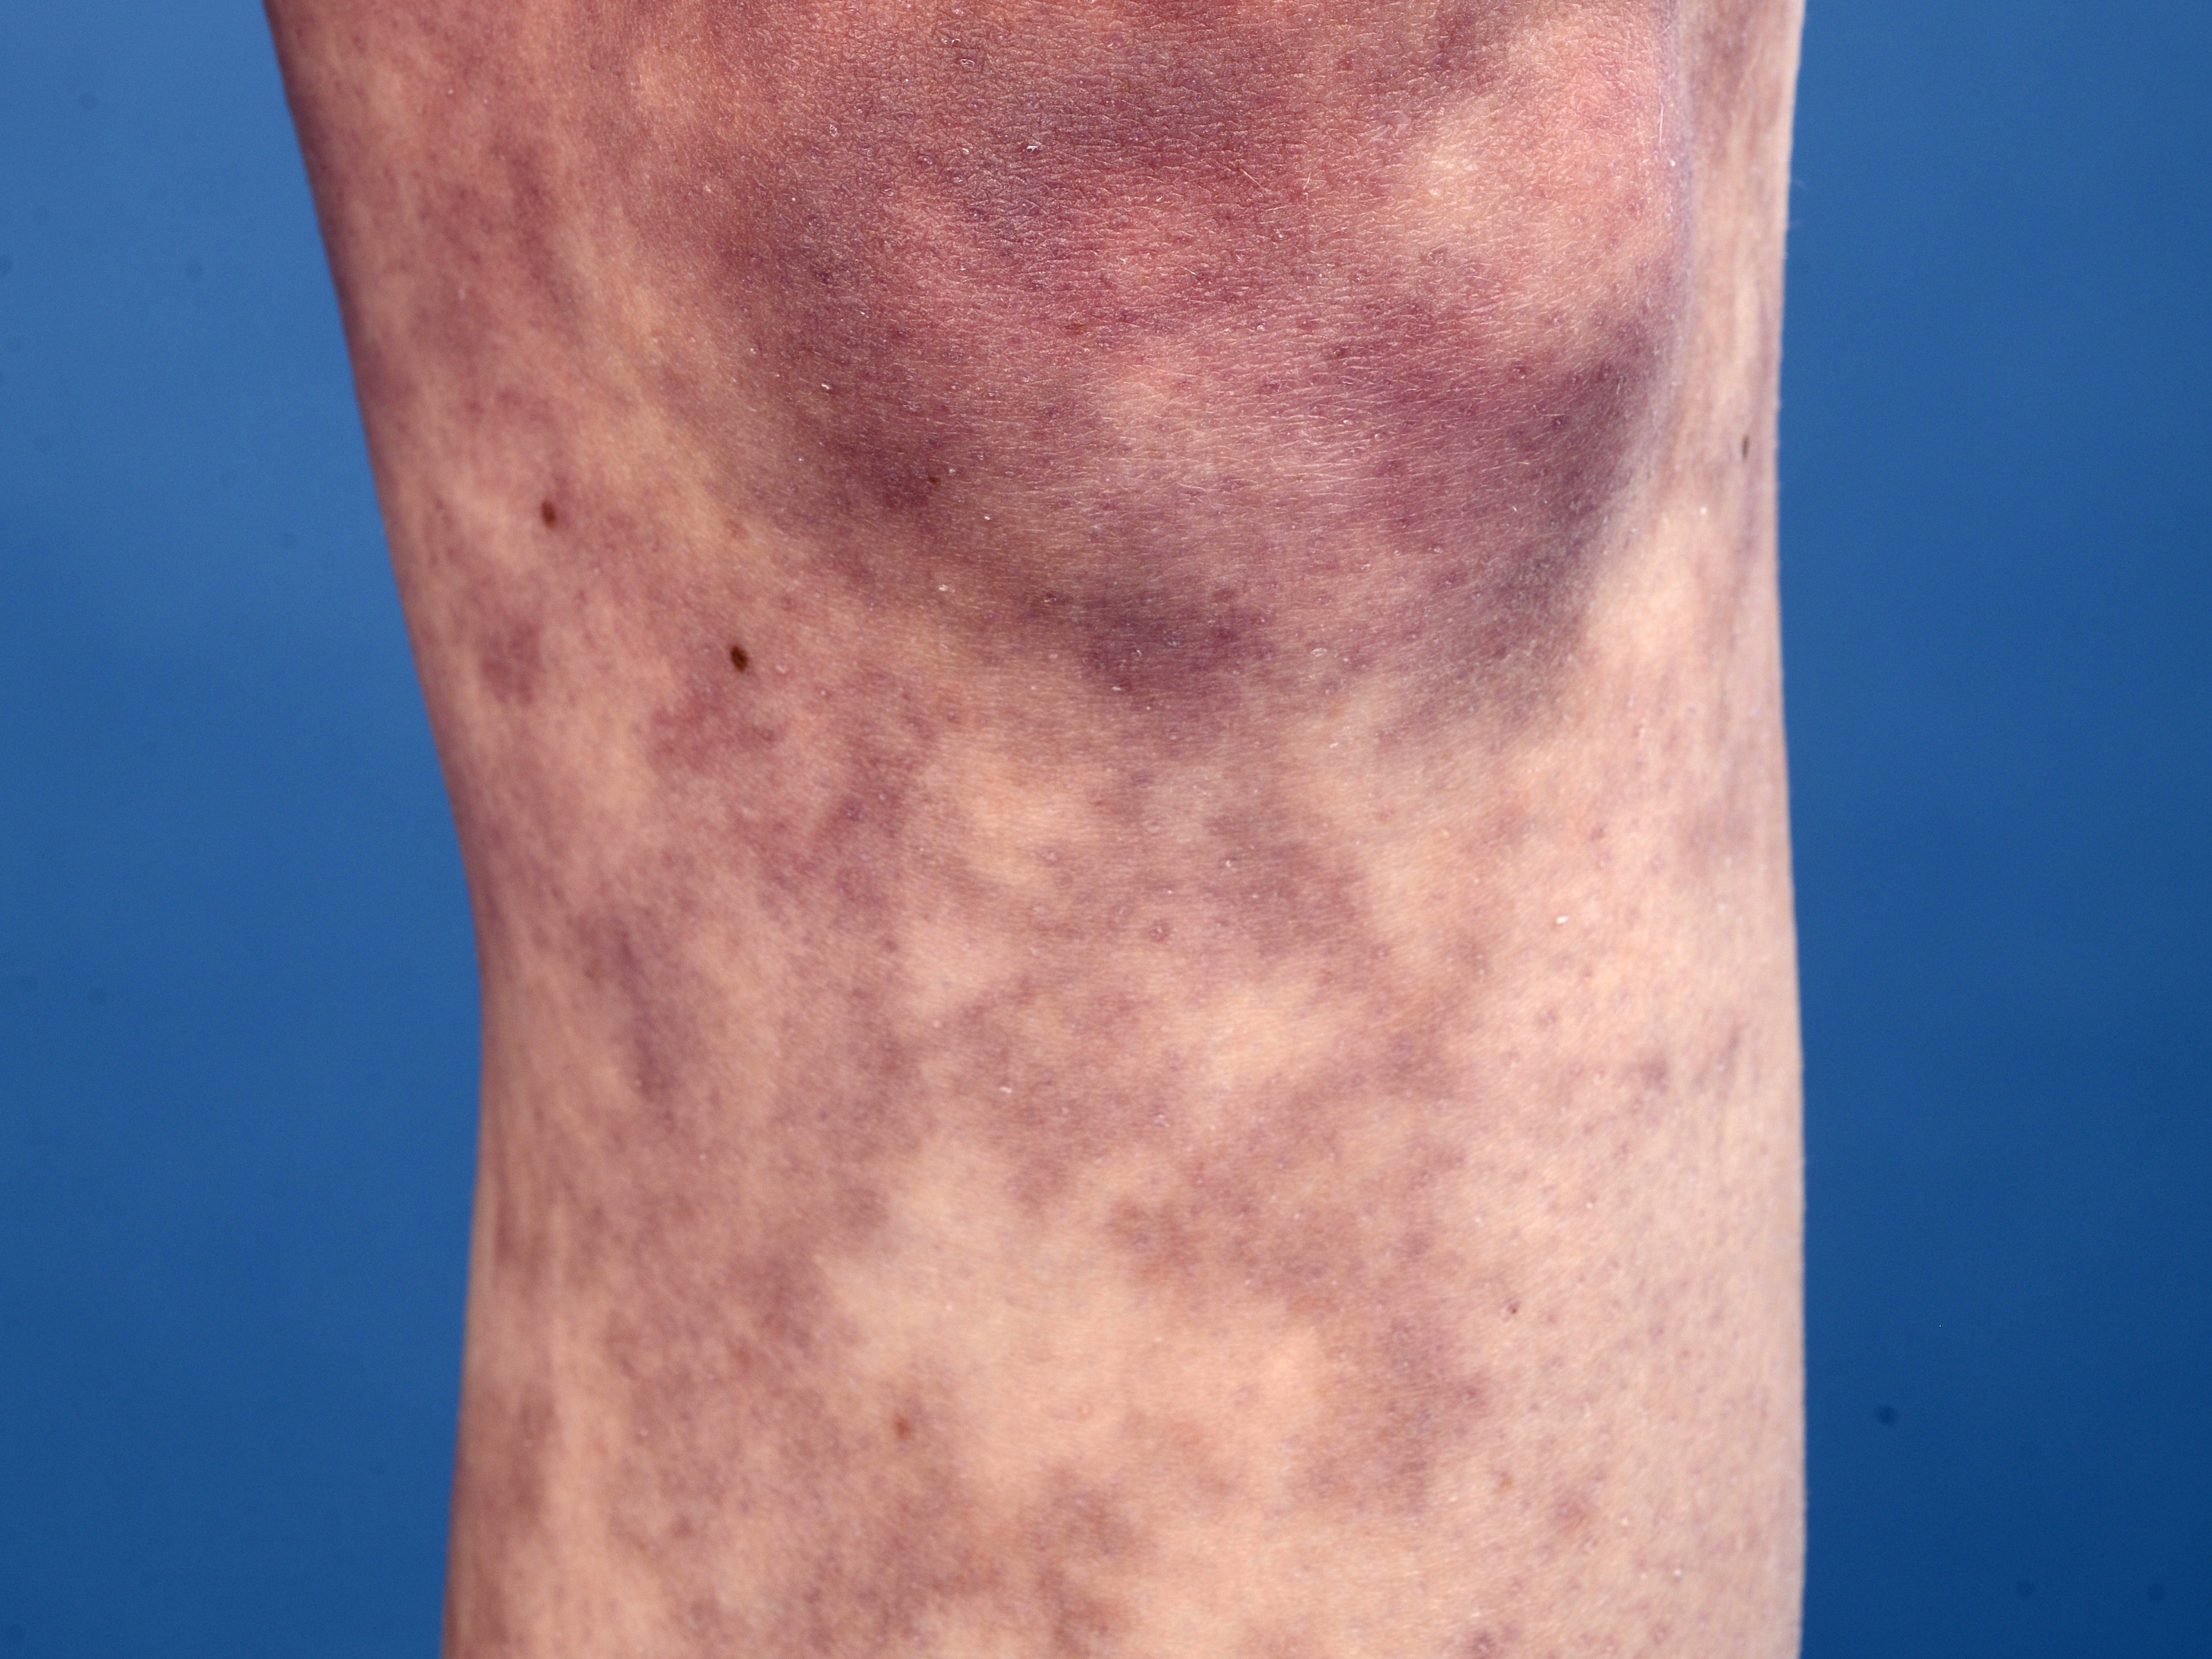

Klinische symptomen:Diepe

veneuze trombose, tromboflebitis, arteriële trombose,

livedo reticularis, capillaritis,

Raynaudfenomeen, acrocyanose, cutane ulcera, cerebrale doorbloedingsstoornissen,

![anti-fosfolipiden syndroom (click on photo to enlarge) [source: www.huidziekten.nl] anti-fosfolipiden syndroom](../../../images/aps1z.jpg) |

![anti-fosfolipiden syndroom (click on photo to enlarge) [source: www.huidziekten.nl] anti-fosfolipiden syndroom](../../../images/aps2z.jpg) |

| anti-fosfolipiden

syndroom |

anti-fosfolipiden

![livedo reticularis bij anti-fosfolipiden syndroom (click on photo to enlarge) [source: www.huidziekten.nl] livedo reticularis bij anti-fosfolipiden syndroom](../../../images/aps-livedo-reticularis-1z.jpg) |

![livedo reticularis bij anti-fosfolipiden syndroom (click on photo to enlarge) [source: www.huidziekten.nl] livedo reticularis bij anti-fosfolipiden syndroom](../../../images/aps-livedo-reticularis-2z.jpg) |

livedo

reticularis |